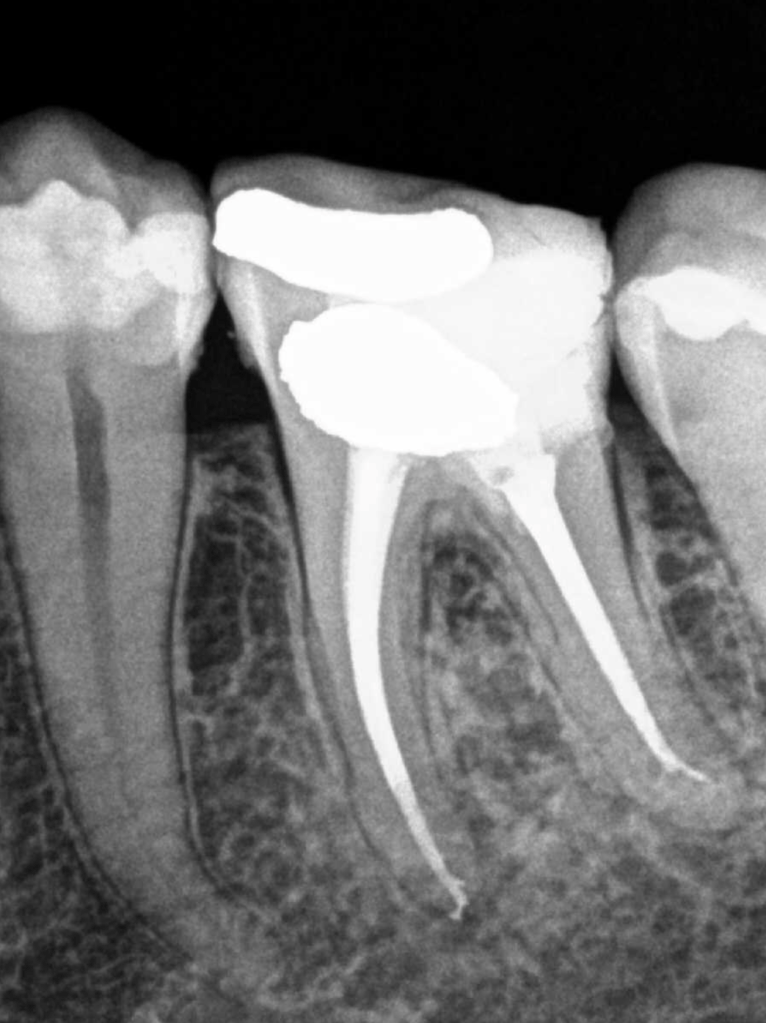

Reco preendo + 4 conductos molar superior

Retratamiento Molar Superior

Retratamiento Primer Molar Superior